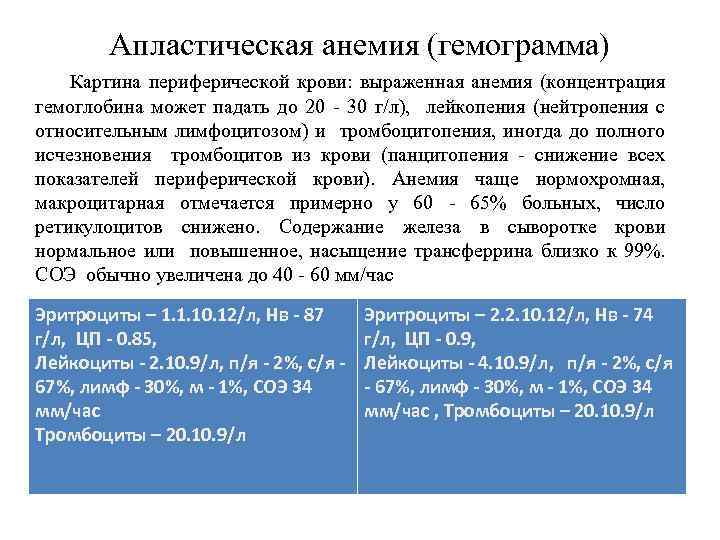

Апластическая анемия (гемограмма) Картина периферической крови: выраженная анемия (концентрация гемоглобина может падать до 20 - 30 г/л), лейкопения (нейтропения с относительным лимфоцитозом) и тромбоцитопения, иногда до полного исчезновения тромбоцитов из крови (панцитопения - снижение всех показателей периферической крови). Анемия чаще нормохромная, макроцитарная отмечается примерно у 60 - 65% больных, число ретикулоцитов снижено. Содержание железа в сыворотке крови нормальное или повышенное, насыщение трансферрина близко к 99%. СОЭ обычно увеличена до 40 - 60 мм/час Эритроциты – 1. 1. 10. 12/л, Нв - 87 г/л, ЦП - 0. 85, Лейкоциты - 2. 10. 9/л, п/я - 2%, с/я 67%, лимф - 30%, м - 1%, СОЭ 34 мм/час Тромбоциты – 20. 10. 9/л Эритроциты – 2. 2. 10. 12/л, Нв - 74 г/л, ЦП - 0. 9, Лейкоциты - 4. 10. 9/л, п/я - 2%, с/я - 67%, лимф - 30%, м - 1%, СОЭ 34 мм/час , Тромбоциты – 20. 10. 9/л